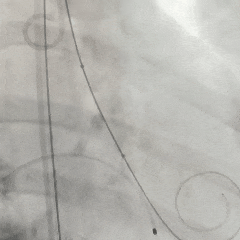

全展开后多角度根部造影:瓣膜深度形态合适,冠脉灌注良好,少量瓣周漏,选择解锁脱钩

脱钩后造影评估:瓣膜深度可,展开良好,少量瓣周漏

外周造影检查,血管无损伤